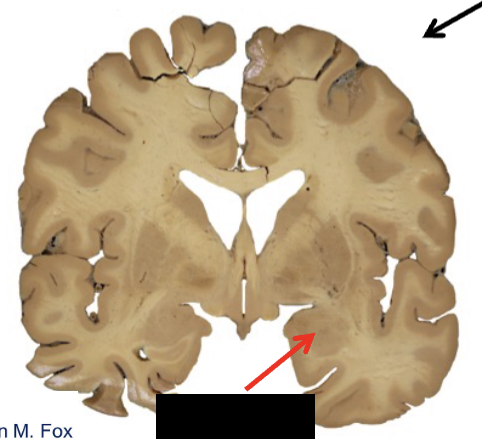

limbic system

what structure is this?

amygdala

hippocampal formation

the amygdaloid complex contains multiple nuclei

lcoated in the _____ lobe, rostral of the hippocampal formation, at the anterior end of the temporal horn of the lateral ventricle

function: general limbic emotions and behaviors, fear, anger, satiety, and environmental contexts

stimulation: fear, rage

_____: highly variable responses, passivity, and hypersexuality

temporal, ablation